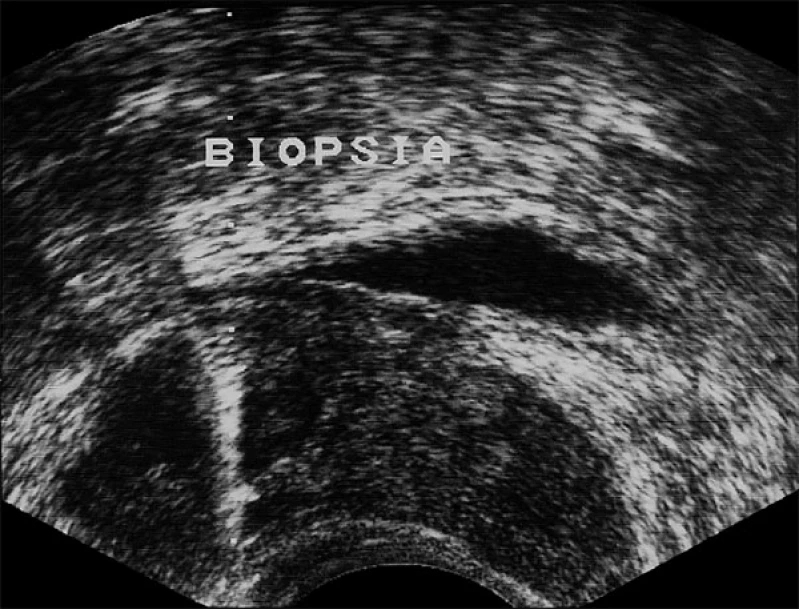

biopsia de próstata

A biópsia de próstata é um procedimento realizado para diagnosticar o câncer de próstata. Durante o procedimento, o médico insere uma agulha na próstata para retirar pequenas amostras de tecido. Essas amostras são examinadas em laboratório para determinar se há células cancerígenas presentes. A biópsia é geralmente realizada após um exame de sangue de PSA elevado ou um exame retal anormal. Embora a biópsia possa ser desconfortável, é um procedimento seguro e eficaz para diagnosticar o câncer de próstata. Se você tiver dúvidas sobre a biópsia de próstata, consulte um urologista. A DK Urologistas oferece serviços de diagnóstico e tratamento de câncer de próstata.